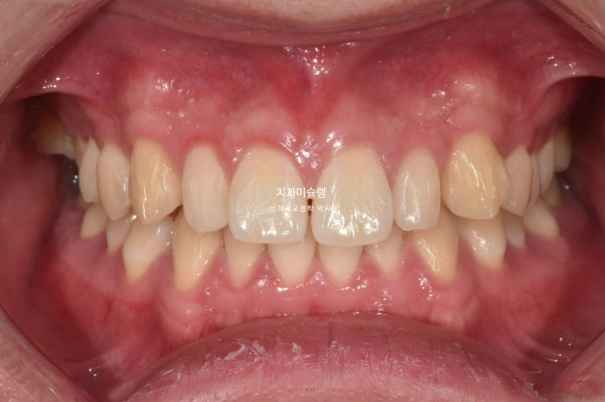

2022년 10월 비대칭으로 내원하신 분입니다.

중심선 불일치, 왜소치로 인한 벌어짐, 송곳니 덧니 등이 보입니다.

22.10